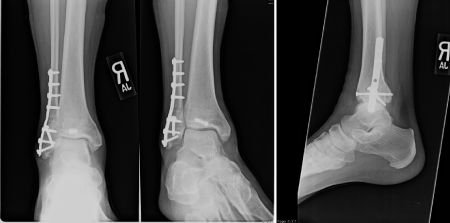

Figure 3 AP, Mortise & Lateral of Right ankle post-reduction with plating of the distal fibula, syndesmotic screw fixation and Anterior to Posterior screw fixation of the posterior malleolus.

We performed a reduction maneuver of the tibiotalar joint with the intent of reducing the distal fragment to the proximal. This maneuver successfully brought the two fragments together but also reduced the proximal segment to the tibia. We did not have to perform an independent maneuver for the proximal segment as has been described in other case reports. Once reduced the fibula was clamped and treated like a typical fibula fracture with lag screw and neutralization plate application. The posterior malleolus was clamped and fixed with an anterior to posterior 4.0mm cannulated partially threaded cancellous screw. The syndesmosis was then stressed in the coronal and sagittal planes and found to be unstable. This was then secured with a 3.5mm cortical screw. The wound was closed in standard layered fashion and a well padded splint was applied. The patient was kept non-weight bearing until the syndesmotic screw was removed at 10 weeks post operatively.